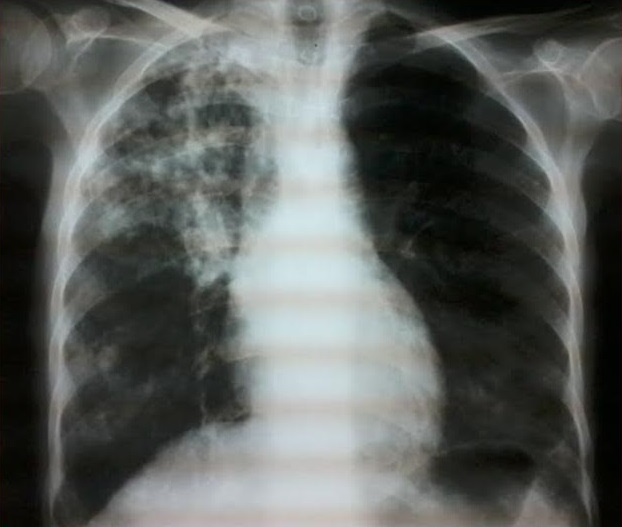

La fréquence de la tuberculose est beaucoup plus élevée au cours des maladies systémiques que dans la population générale, il s'agit le plus souvent de la réactivation d'une tuberculose latente. A côté de l'immunodépression induite par la maladie sous-jacente, il faut souligner le rôle favorisant des glucocorticoïdes et des traitements immunosuppresseurs. Nous rapportons un cas de tuberculose pulmonaire compliquée d'une dilatation des broches (DDB) au cours d'une entité très rare appelée rhupus syndrome (lupus érythémateux systémique et polyarthrite rhumatoïde). Une patiente âgée de 41 ans suivie depuis 10 ans pour rhupussyndrome, elle était mise sous corticothérapie à fortes doses associée à des anti paludéens de synthèse et du méthotrexate. L'évolution ultérieure était marquée par l'amélioration de la symptomatologie cutanée et articulaire avec l'apparition d'une symptomatologie respiratoire trainante et récidivante. Le dernier épisode était marqué par une fièvre à 39°, une asthénie, un amaigrissement, une dyspnée et une toux. Le bilan tuberculeux était positif et la radiographie thoracique montrait un foyer de dilatation des bronches lobaire supérieur droit séquellaire d'une tuberculose pulmonaire. La patiente était mise antituberculeux avec bonne amélioration clinique et radiologique.